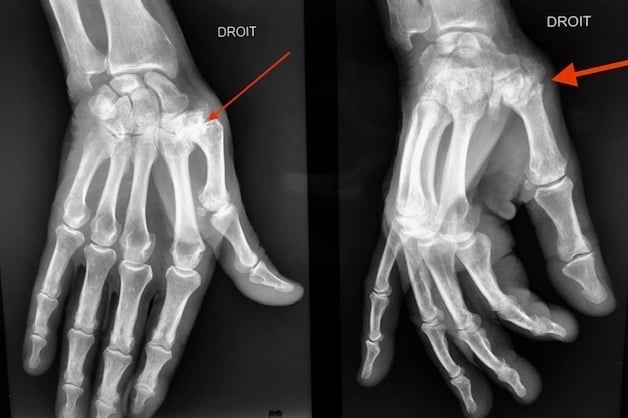

Les fractures ouvertes, ou déplacées avec troubles de rotation seront traitées chirurgicalement. Le choix du traitement chirurgical est fonction de l’os atteint, du siège et du type de fracture.

Schématiquement, la stabilisation après réduction de la fracture est faite soit par broche soit par plaque. Cette chirurgie réalisée en ambulatoire sous anesthésie du bras, doit permettre une rééducation précoce afin de restaurer la fonction de la main. Des pansements sont à faire réaliser par infirmière durant deux à trois semaines. La rééducation sera donc précoce afin de limiter la raideur.

Plaque M1